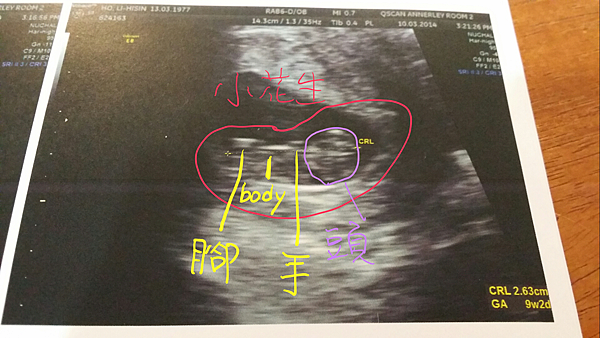

拿著醫生給的超音波referral,打了第一家電話,就幸運地約到當天下午三點。我們兩個都非常緊張焦慮,所以越少的等待in between對我們真的是越好。喝了一坨水忍著尿意去到照超音波的地方,放射師開始頭頭有道解說起來。說真的一開始我們只是霧裡看花,聽她說這個像花生一樣的就是你們的baby,這個是頭,還可以聽到心跳(每分鐘180下--好快!!)。我是又驚奇又興奮,而且她說小花生在我的肚子裡,到今天為止已經9個禮拜又兩天了!!天哪,想到一二月的玩樂,包括跳水、騎大象、浮潛、騎腳踏車等等等等,爹娘真是緊張萬分、捶胸頓足、不知如何面對江東母老(何媽媽與杜媽媽)...

看到最後一張,放射師細心的解說,這個solid的白色實線看起來是他的小手、小腳還有身體 (如上圖二),因為才剛剛開始發展,所以都還很小。我之前還問了兩個愚蠢問題,問說小孩是先長頭再長身體嗎?(答案是先有心跳...我真是蠢,孩子啊千萬不要繼承你媽)然後我又問他有沒有在正確的地方著陸,因為我們很怕什麼子宮外孕的(總不太相信自己會這麼幸運又順利地懷上小baby)。放射師笑笑地說他好好地待在子宮裡,而且還會動,應該很健康。就在她說明完哪裡是小腳的時候,那個疑似小腳的白線,就像要證實一樣的,在我們面前動了兩動!!這一下衝擊真不是普通的大,我又很蠢地問說那是他在動嗎?放射師小姐還是很親切地說沒錯。然後小花生爸媽就完全被這英勇的抖腳(踢腿?)給征服了,進入感動陶醉飄飄欲仙、如入無人之境的境界...